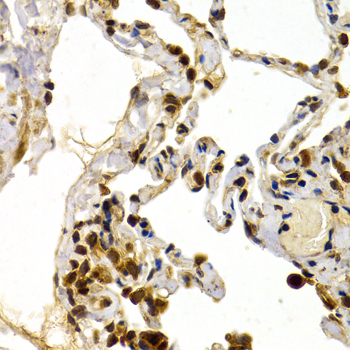

Immunohistochemistry of paraffin-embedded human normal lung using TFDP1 antibody at dilution of 1:200 (400x lens).